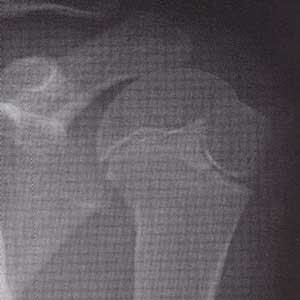

正常の肩関節 右と左 骨頭のところに線が入って見えるのも正常→骨端線 コッタンセン

痛んでいる肩関節(写真左側)→リトルリーガーズショルダー

投球側の骨頭 コットウ がずれています。 (写真右側は非投球側)